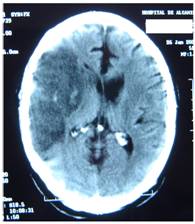

Figure 4 represents and example of ischemic stroke and hemorrhagic stroke on baseline and delayed CT with edema developing after 48 hours.

FIGURE 5

A. CT on admission. Hemorrhagic stroke presenting with headache and left hemiplegia. CRP level: 3.23 mg/dL. NT-PBNP level: 66.3 pmol/L. B. CT scan after 48 hours in the same patient. See the surrounding hypoatenuation of the hematoma with increased mass-effect. CRP level: 22.6. NT-PBNP level: 197 pmol/L.